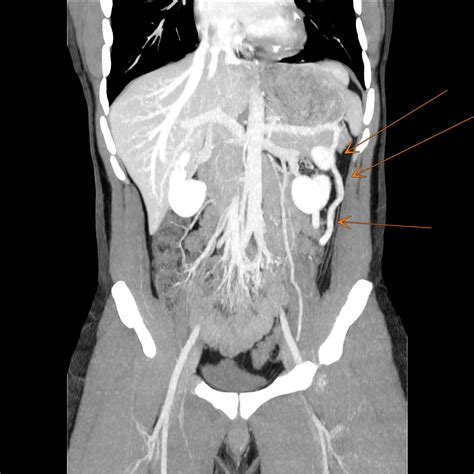

Understanding vascular anomalies can be complex, and one condition that often goes misdiagnosed due to its vague and varied symptoms is Nutcracker Syndrome. If you have been searching for answers regarding persistent pelvic pain, flank discomfort, or hematuria, you might be asking yourself, "What is Nutcracker Syndrome?" At its core, this is a rare venous compression disorder that occurs when the left renal vein is squeezed between two major arteries: the abdominal aorta and the superior mesenteric artery. This compression creates a "nutcracker" effect, impeding the normal flow of blood from the left kidney back toward the heart, leading to a variety of debilitating symptoms.

To grasp the mechanical nature of this condition, it is helpful to visualize the anatomy of the abdomen. The left renal vein travels horizontally across the abdomen to deliver blood from the left kidney into the inferior vena cava. In patients with Nutcracker Syndrome, the angle at which the superior mesenteric artery branches off the aorta is unusually narrow. This anatomical narrowing acts like a clamp, compressing the renal vein.

CT Angiography (CTA) Provides 3D images to measure the precise angle of the artery and the vein diameter.